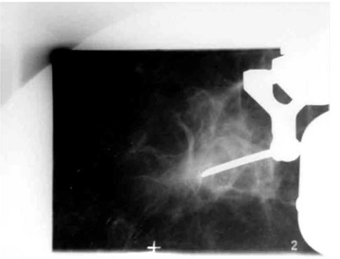

אמינות: סגוליות הממוגרפית המדווחת היא 96% ואילו הרגישות 80%-75%. Positive predictive value הוא 50%-10%. אין ספק שהממוגרפיה היא מכשיר בינוני לסיקור אוכלוסייה לגילוי מוקדם של סרטן השד. אולם זה המכשיר היחיד כיום (תמונה 19.12).

הבדיקה החשובה ביותר לגילוי מוקדם של שאתות השד היא הממוגרפיה. בבדיקה זו ניתן להדגים את רקמת השד, סמיכות הרקמה, הסתיידויות, עובי העור, צורתו וצל כלי הדם. צל בעל סמיכות יתר המכיל בתוכו מיקרוקלסיפיקציות במספר רב, בעל גבולות בלתי סדירים, כמו קרניים, עם זנב של רקמה סמיכה היוצאת ממנו, ריבוי והדגשה של כלי הדם או התעבות העור ושקיעת הפטמה, כולם מהווים סימנים מחשידים לקיום שאת ממארת בשד (תצלומים 22.12, 23.12). בהגדלה ניתן לראות את הסימנים לממאירות בצורה ברורה יותר (תצלום 24.12).

הסיבות אשר בעטיין נגע מסוים איננו ניתן למישוש הן: שאת קטנה, שאת המתבטאת רק בהסתיידויות זעירות ללא גוש (תצלום 25.12), שד גדול או מגורגר המקשה על הבדיקה הקלינית. הממוגרפיה, למרות יכולתה לגלות נגעים בלתי ניתנים למישוש, איננה בדיקה חד-משמעית וסגוליותה נמוכה. מחד גיסא, גוש סמיך בעל שוליים בלתי סדירים, עם הקרנת קוריות לסביבה מעיד בביטחון על תהליך ממאיר. מאידך גיסא, הסתיידויות גסות, הסתיידויות כיסתיות או הסתיידויות פסיות סדירות וכן נגעים בעלי סמיכות דומה לזו של שומן, מצביעים על תהליך שפיר.